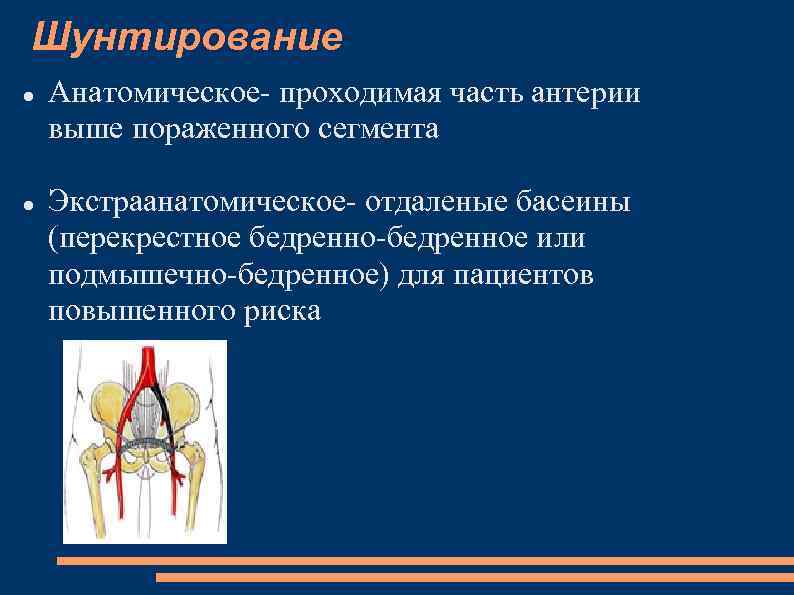

Шунтирование Анатомическое- проходимая часть антерии выше пораженного сегмента Экстраанатомическое- отдаленые басеины (перекрестное бедренно-бедренное или подмышечно-бедренное) для пациентов повышенного риска